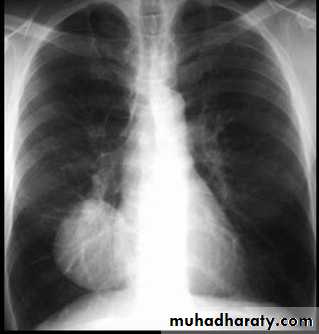

• Alveoiar oedema (‘Bat’s wings’)

• Kerlev B lines (interstitial oedema)

• Prominent upper lobe vessels

• Cardiomegaiy

• Pleura

• effusion

Kerley A lines (Arrows), Kerley B lines (arrowheads)